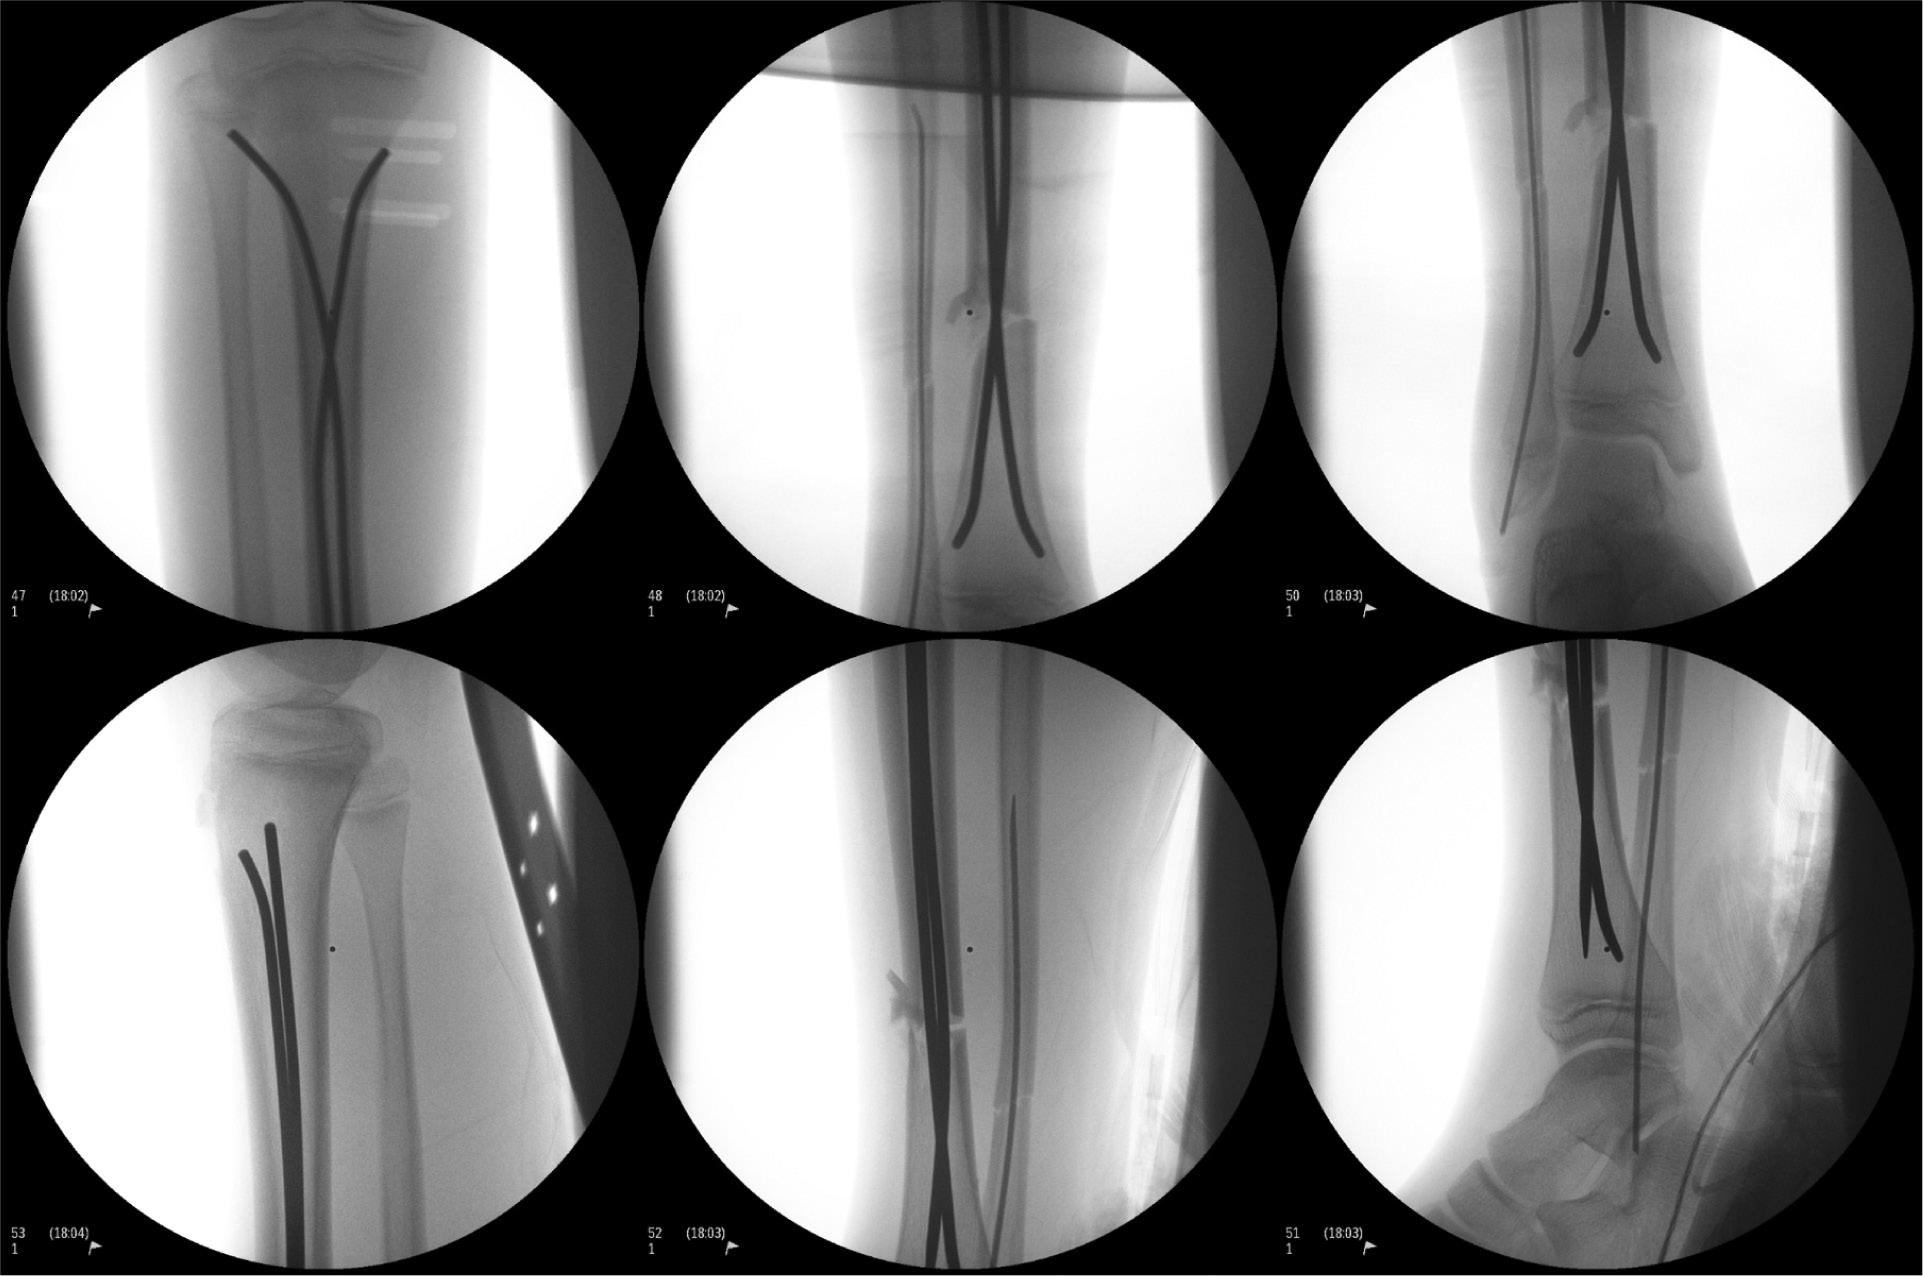

- Imaging:

Final fluoroscopy:

- Difficulty with closed reduction, due to some of the comminution. Able to achieve good reduction by applying axial traction using radiolucent triangles and stack of blue OR towels.

- Tibia: 3.5 mm stainless steel ESINs

- Notice distally how the nails cross essentially right at the fracture. This is not ideal, but sometimes there is no way around this.

- Fibula: 1.5 mm titanium ESIN

- Decided to augment our tibial fixation with fixation of the fibula due to there being lateral comminution at the fracture on the tibia. We thought that by adding some stiffness/fixation to the fibula, we could help prevent the tibia from translating laterally and/or falling into valgus.

- We initially tried to send a 2.0-mm K-wire up the fibula, but this was a little bit too stiff and not quite long enough.